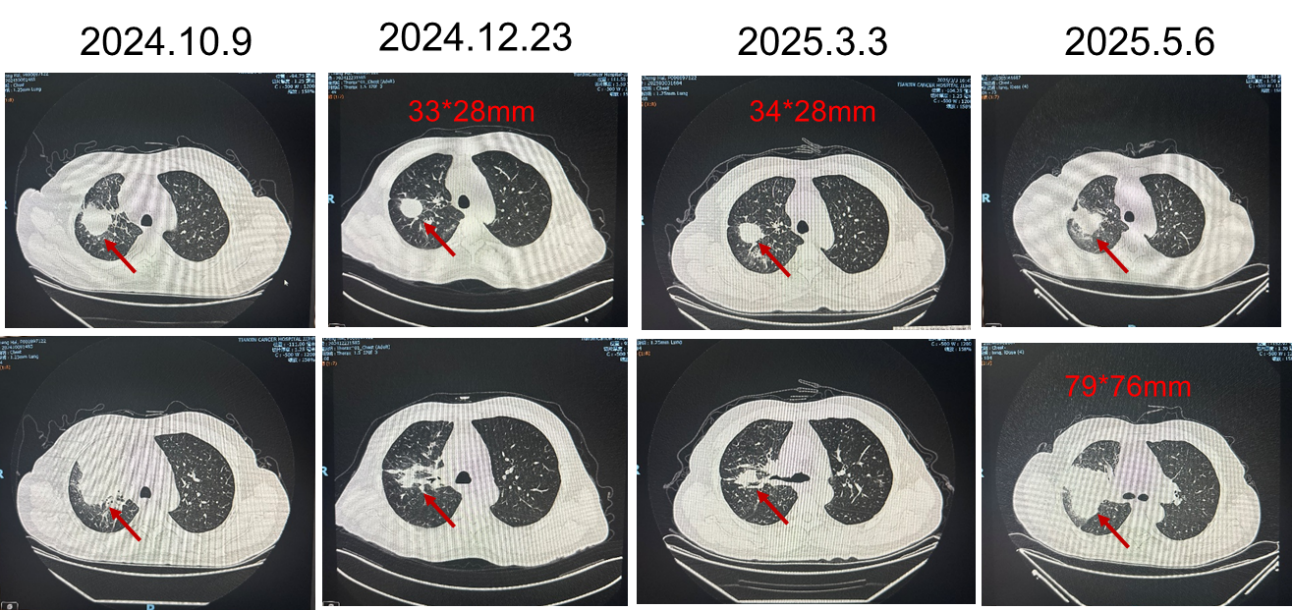

2024年10月9日开始给予长春瑞滨软胶囊100mg d1,8+奈达铂60mg d1-2+血管内皮抑制素75mg d1-2,60mg d3治疗5周期;后因血小板减低,行长春瑞滨软胶囊40mg tiw节拍化疗+血管内皮抑制素75mg d1-2,60mg d3维持治疗3周期。并于2024-11-06行脑转移瘤射波刀治疗1次。

疗效评估:PD。

PFS3:6个月27天。

治疗过程中的影像学变化: